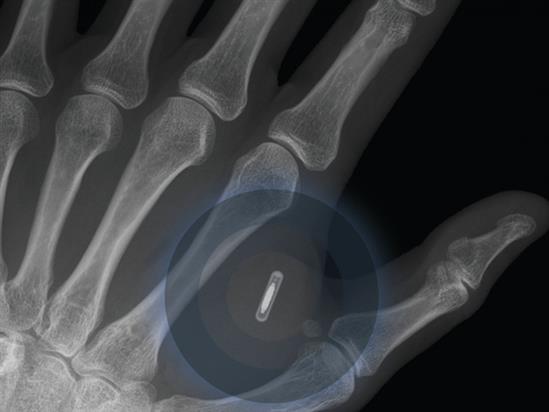

6. Thiết bị di động có thể được cấy dưới da vào năm 2025.

Ý nghĩa của câu "Mang điện thoại theo người" sẽ có chút thay đổi vào năm 2023, khi chúng ta thành công trong việc gài các thiết bị di động vào cơ thể.

Vẫn còn nhiều tranh cách xung quanh việc cấy máy móc vào cơ thể người.

Khoảng 80% người được hỏi dự đoán rằng điện thoại di động sẽ được cấy ghép vào cơ thể trong khoảng 7 năm nữa. Tất nhiên, ngoài việc nghe gọi, nó sẽ có những khả năng của một thiết bị theo dõi sức khỏe, thậm chí là đọc được sóng não và chuyển hóa chúng thành tín hiệu lời nó. Và tới năm 2025, công nghệ này sẽ được sử dụng rộng rãi.